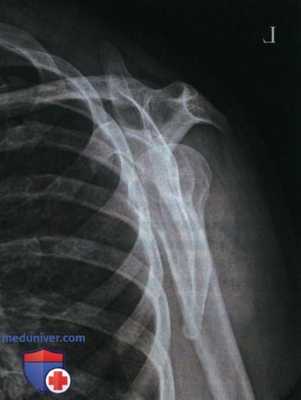

Пример анализа рентгенограмм плечевого сустава в ПЗ проекции

1. Анализ. Верхний угол лопатки визуализируется выше середины ключицы. Верх срединной коронарной плоскости был наклонен вперед.

2. Коррекция. Выпрямите верх срединной коронарной плоскости так, чтобы он стал параллелен ПИ.

1. Анализ. Медиальный конец ключицы повернут в сторону от латерального края позвоночного столба; суставная впадина лопатки видна почти в профиль, отображается лишь небольшая часть суставной поверхности; верхнелатеральный край лопатки накладывается на грудную клетку; отмечается продольное проекционное укорочение ключицы. Туловище было повернуто в сторону исследуемого плечевого сустава. Большой бугорок виден в профиль. Если плечо не поворачивать, то большой бугорок будет виден частично в профиль.

2. Коррекция. Поверните туловище в противоположную сторону от исследуемого плечевого сустава (в ПЗ проекцию) так, чтобы плечевые суставы находились на равном расстоянии от ПИ, и срединная коронарная плоскость была параллельна ПИ.

1. Анализ. Тело лопатки выдвинуто из-под грудной клетки и поперечно проекционно укорочено. Видна большая часть суставной впадины лопатки, и медиальный конец ключицы накладывается на позвоночный столб. Туловище было повернуто в противоположную сторону от исследуемого плечевого сустава. Верхний угол лопатки визуализируется выше середины ключицы. Верх срединной коронарной плоскости был наклонен вперед. Малый бугорок виден в профиль. Надмыщелки плечевой кости располагались перпендикулярно ПИ.

2. Коррекция. Поверните туловище в сторону исследуемого плечевого сустава (в ПЗ проекцию) так, чтобы плечевые суставы располагались на равном расстоянии от рентгеновского стола; выпрямите срединную коронарную плоскость, расположив ее параллельно ПИ; поверните надмыщелки плечевой кости наружу до угла 45° с ПИ.